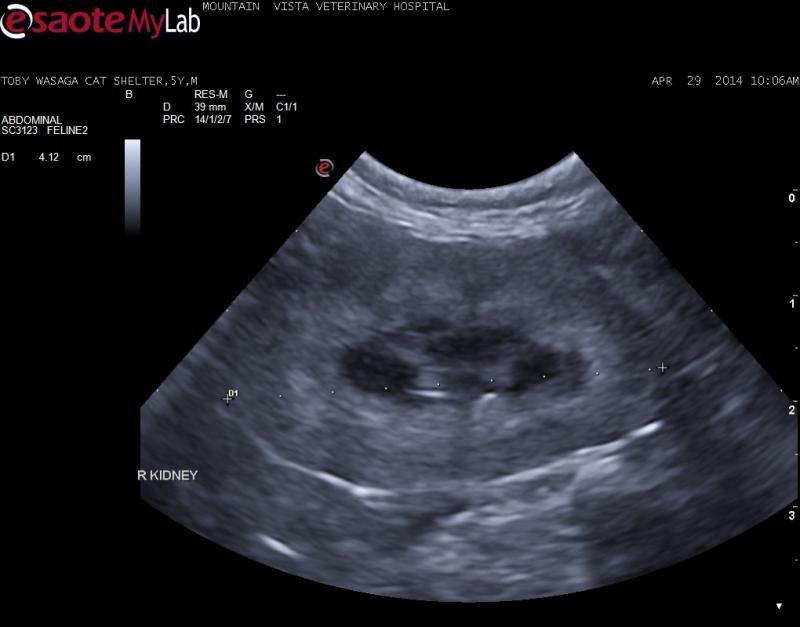

– 5 year old shelter adopted cat severe azotemia, anemia, Feleuk/FIV negative, corono virus positive (I know not helpful)

– no history of toxin ingestion

– thick, hyperechoic renal cortices – no lymphadenopathy and rest of scan unremarkable

lymphoma, FIP, chronic nephritis?

– patient will likely be euthanized due to clinical status but would you FNA these kidneys?

Thick cortices, irregular

Thick cortices, irregular C/M junction, swollen contour of your 3 diffs “lymphoma, FIP, chronic nephritis” I put chronic intersitial nephrosis first and dry FIP second lymphoma distant third just to put a third one in there as the contour and cm structure is still holding more consistent with chronicicity and inflammatory disease and less so with neoplasia. Uniform parenchymal remodeling and expansion is happening. Lymphoma distorts structure, inflammatory fills the sack and remodels if that makes sense. There is a medullary rim sign which FIP can do. Needs core Bx pre or post portem. FNA will rule out lsa and may give insight to granulomatous for FIP but rarely definitive dx on fna but as i find new and select cytologists this may change.

see the renal lymohoma in the sonopath search